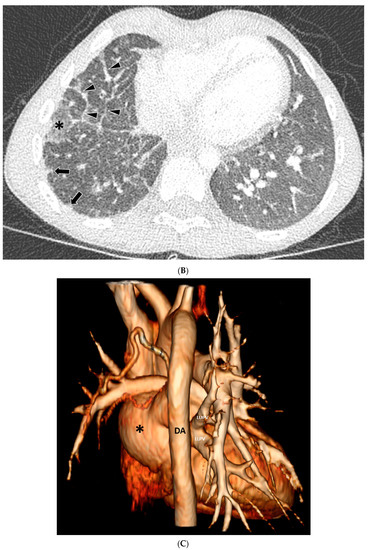

| GGO | 19/20 (95%) |

| Septal Thickening | 7/20 (35%) |

| Pleural Thickening | 17/20 (85%) |

| Mediastinal Mass | 17/20 (85%) |